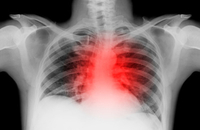

心血管疾病的X线诊断